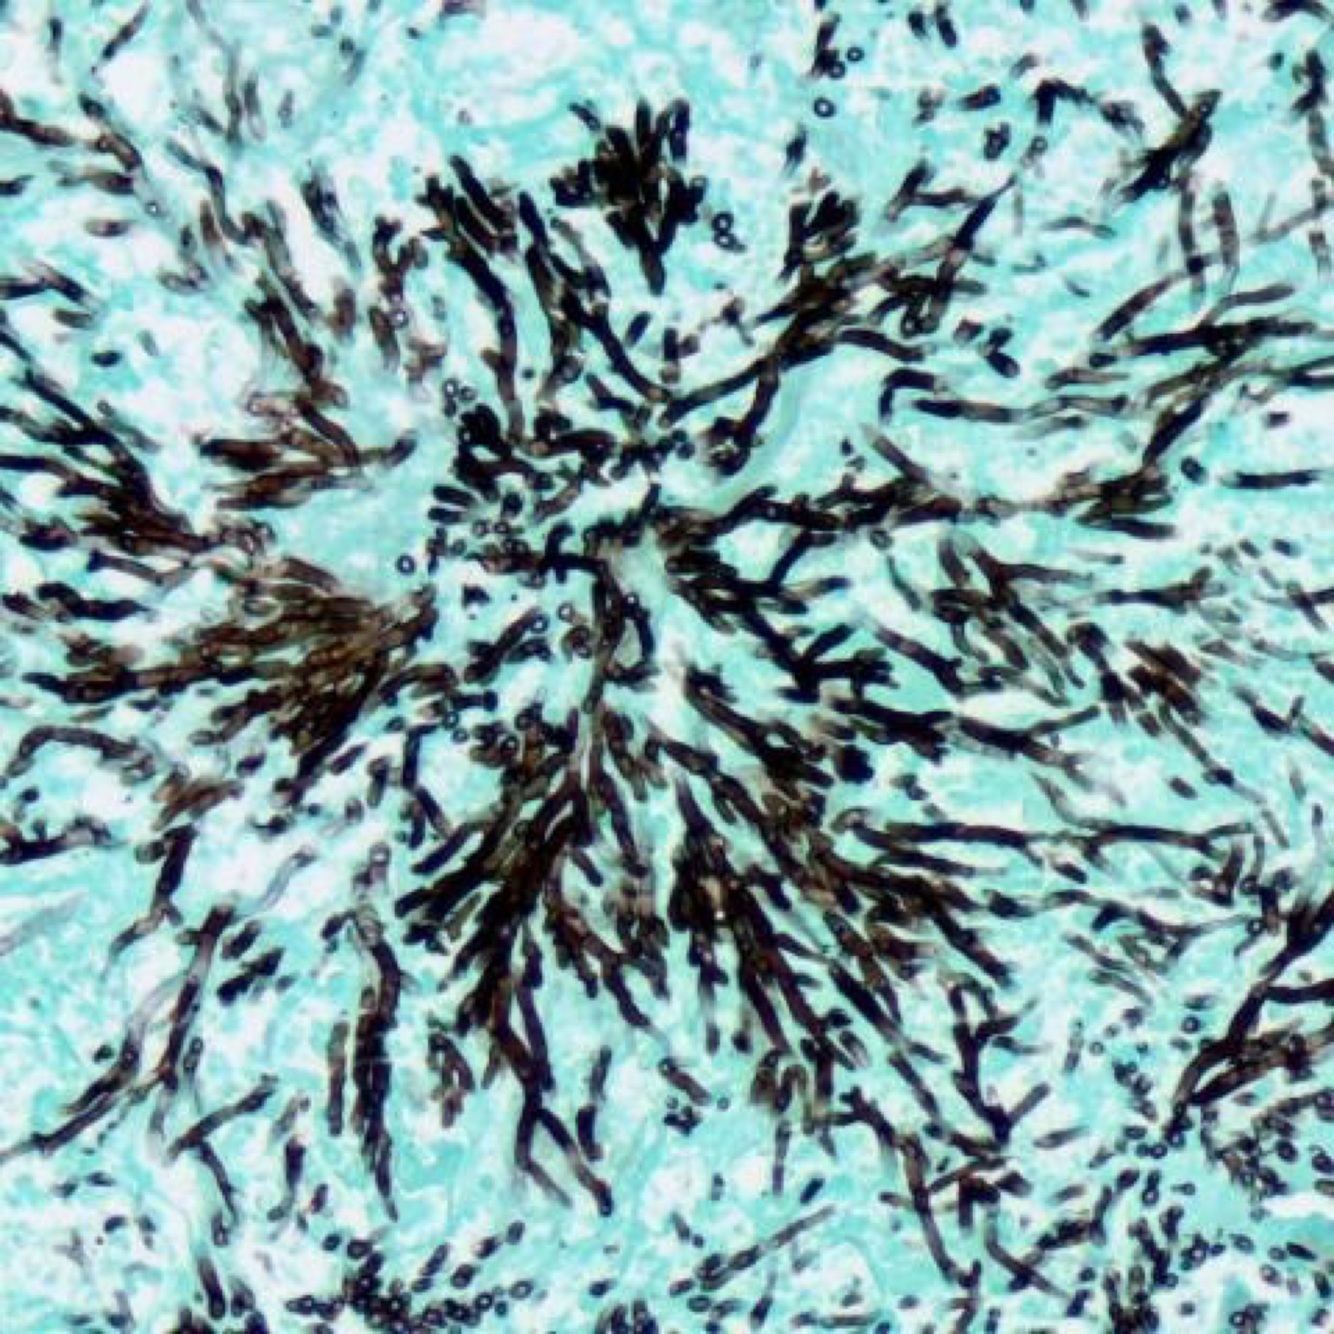

Gomori methanamine silver